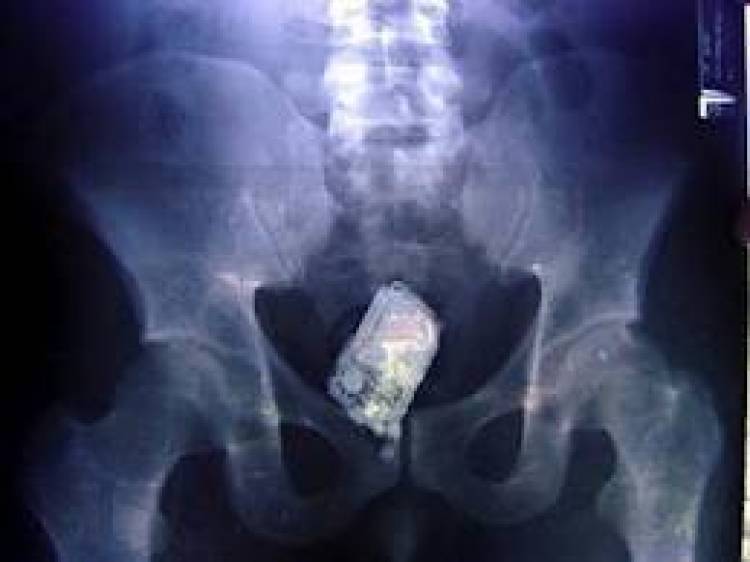

Ο έλεγχος μόνο εύκολη υπόθεση δεν ήταν για τους αστυνομικούς, αφού στις αποσκευές και στις τσέπες του 42χρονου δε βρέθηκε καμία ναρκωτική ουσία. Επειδή όμως υπήρχαν βάσιμες πληροφορίες ότι ο 42χρονος διακινεί ναρκωτικά, οι αστυνομικές έρευνες προχώρησαν ένα βήμα παραπάνω. Μετέφεραν τον ύποπτο για ιατρικές εξετάσεις στο Γενικό Νοσοκομείο Σύρου και μετά από πολύωρη διαδικασία, προέκυψε ότι έκρυβε τα ναρκωτικά σε σημείο του σώματός του και συγκεκριμένα… στον πρωκτό του!

Από την αποβολή των ναρκωτικών ουσιών, διαπιστώθηκε ότι μετέφερε μια νάιλον συσκευασία που περιείχε ηρωίνη βάρους 30 γραμμαρίων, η οποία κατασχέθηκε. Έτσι, η επιμονή των αστυνομικών οδήγησαν στη λύση του μυστηρίου και στην εξιχνίαση της υπόθεσης, μιας ιδιότυπης αποθήκευσης και μεταφοράς ναρκωτικών.